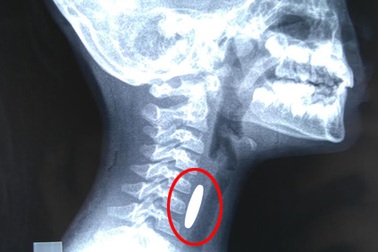

Hóc dị vật thực quản vì... uống thuốcĐi khám bệnh được chẩn đoán cảm cúm và mua thuốc uống, nhưng chỉ sau vài phút uống 3 viên thuốc, nam thanh niên xuất hiện đau giữa ngực, cảm giác đau nhói sau xương ức, nuốt nghẹn, rồi cảm thấy khó thở. Bệnh nhân nhanh chóng được đưa đến khoa Cấp cứu A9 (Bệnh viện Bạch Mai).